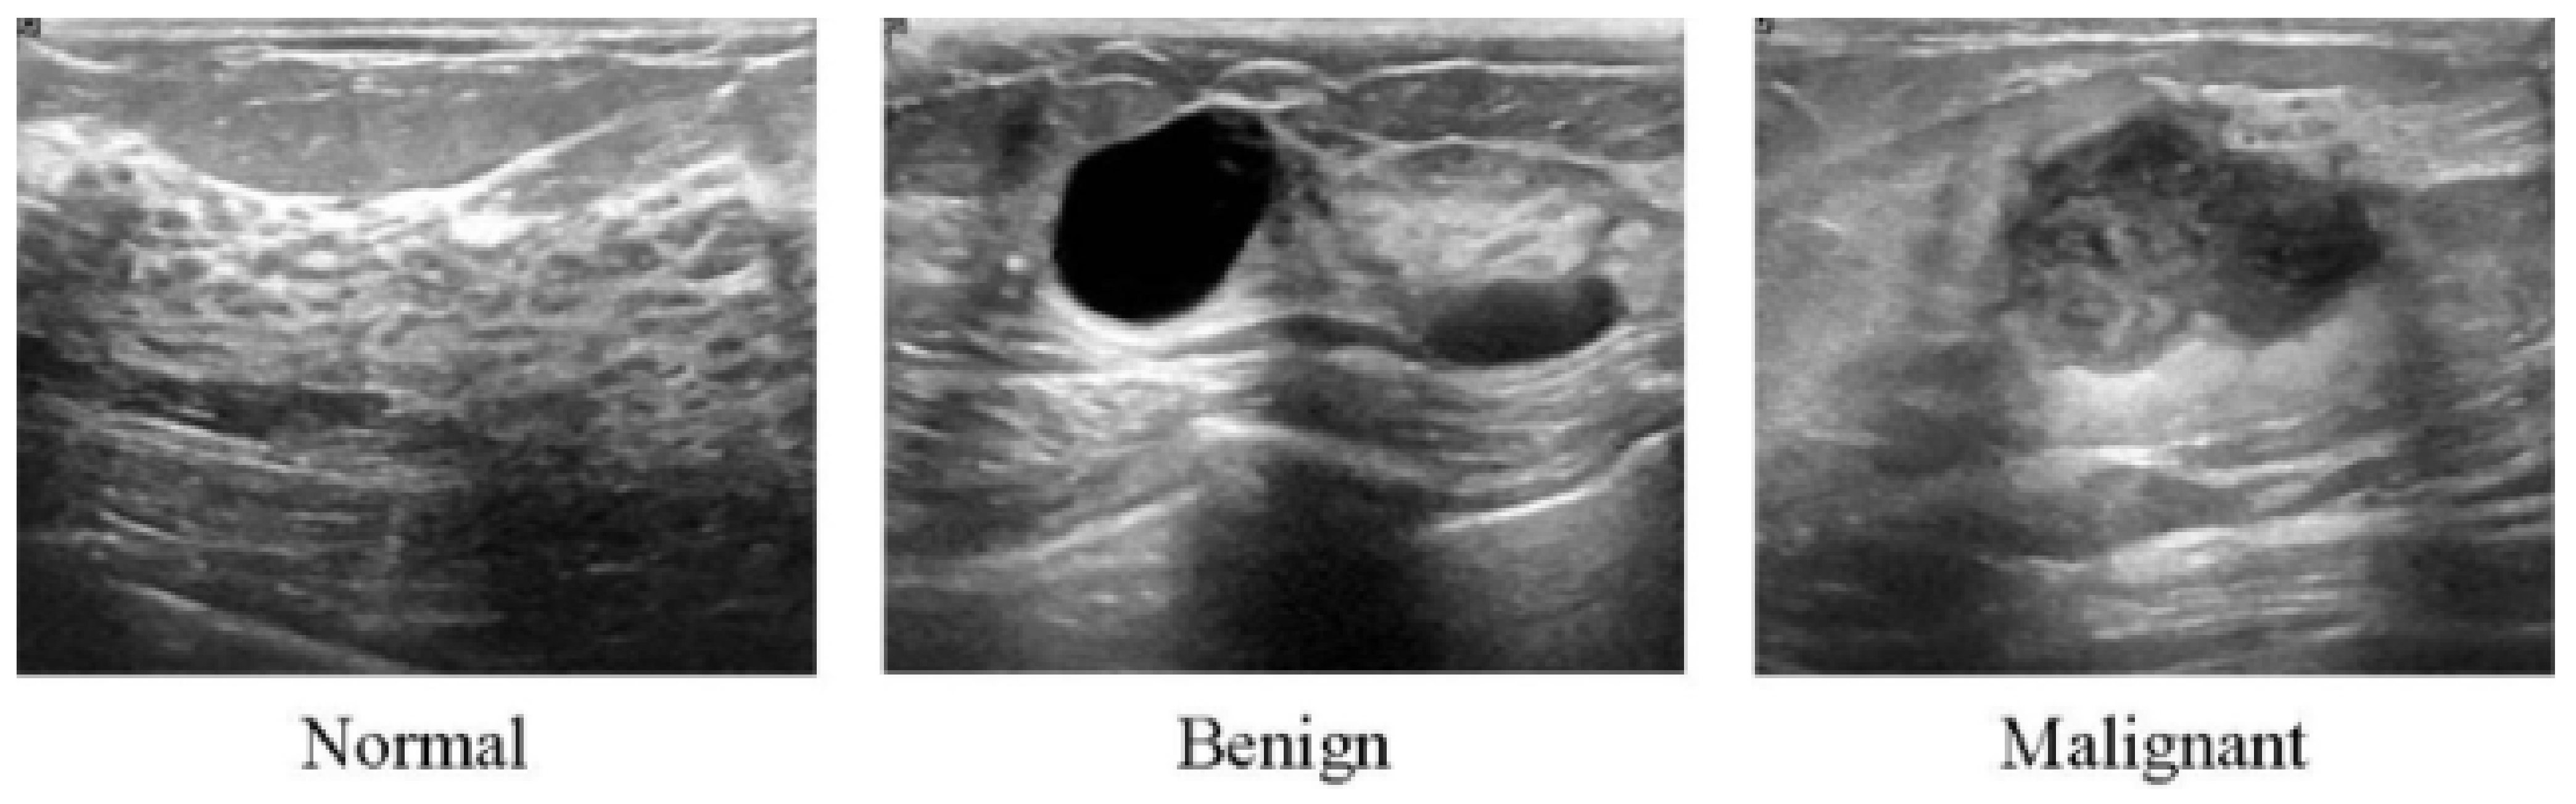

All of the aforementioned modalities can endanger patients and radiologists because of possible overdosage of ionizing radiation, making these approaches slightly risky and unhealthy for certain sensitive patients [62]. Additionally, these methods show low specificity, meaning the low ability to correctly determine a tissue without disease as a negative case. Therefore, although the aforementioned imaging modalities are highly used for early breast cancer detection, the US as a safe imaging modality has been used [62,63,64,65,66,67] (Figure 3). Compared to MMs, the US is a more convenient method for women with dense breasts. It is also useful to characterize abnormal regions and negative tumors detected by MMs [68]. Some studies showed the high accuracy of the US in detecting and discriminating benign and malignant masses [69]. US images are used in three broad combinations, i.e., (i) simple two-dimensional grayscale US images, (ii) color US images with shear wave elastography (SWE) added features, and (iii) Nakagami colored US images without any need for ionizing radiation [70,71]. It is worth noting that Nakagami-colored US images are responsible for the region of interest extraction by better detection of irregular masses in the breast. Moreover, US can be used as a complement to MMs owing to its availability, inexpensiveness compared to other modalities, and it being well tolerated by patients [70,72,73]. In a recent retrospective study, US breast imaging has shown high predictive value when combined with MMs images [74]. US images, along with MMs, improved the overall detection by about 20% and decreased unnecessary biopsy tasks by 40% in total [67]. Moreover, US is a reliable and valuable tool for metastatic lymph node screening in breast cancer patients. It is a cheap, noninvasive, easy-to-handle and cost-effective diagnostic method [75]. However, the US represents some limitations. For instance, the interpretation of US images is highly difficult and needs an expert radiologist to comprehensively understand these images. This is because of the complex nature of US images and the presence of speckle noise [76,77]. To deal with this issue, new technologies have been introduced in breast US imaging, such as automated breast ultrasound (ABUS). ABUS produces 3D images using wider probes. Shin et al. [78] improved how ABUS allows more appropriate image evaluation for large breast masses compared to conventional breast US. On the other hand, ABUS showed the lowest reliability in the prediction of residual tumor size and pCR (pathological complete response) [79]. Table 1 highlights more details about the weaknesses and strengths of the US imaging modality.

Figure 3.

Ultrasound images from breast tissue for normal, benign, and malignant [80].